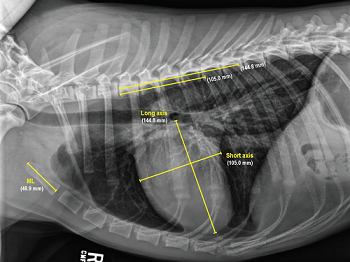

Vertebral Scale System to Measure Canine Heart Size in Radiographs. James Buchanan and Jorg Bücheler. JAVMA January 1995; 206(2): 194-199. Quote: "A method for measuring canine heart size in radiographs was developed on the basis that there is a good correlation between heart size and body length regardless of the conformation of the thorax. The lengths of the long and short axes of the heart of 100 clinically normal dogs were determined with calipers, and the dimensions were scaled against the length of vertebrae dorsal to the heart beginning with T4. The sum of the long and short axes of the heart expressed as vertebral heart size was 9.7 +/- 0.5 vertebrae. The differences between dogs with a wide or deep thorax, males and females, and right or left lateral recumbency were not significant. The caudal vena cava was 0.75 vertebrae +/- 0.13 in comparison to the length of the vertebra over the tracheal bifurcation. ... The major uses of the VHS method are in helping determine whether cardiomegaly exists in dogs with minimal radiographic changes and quantification of the progression of cardiomegaly over time in a glven dog."